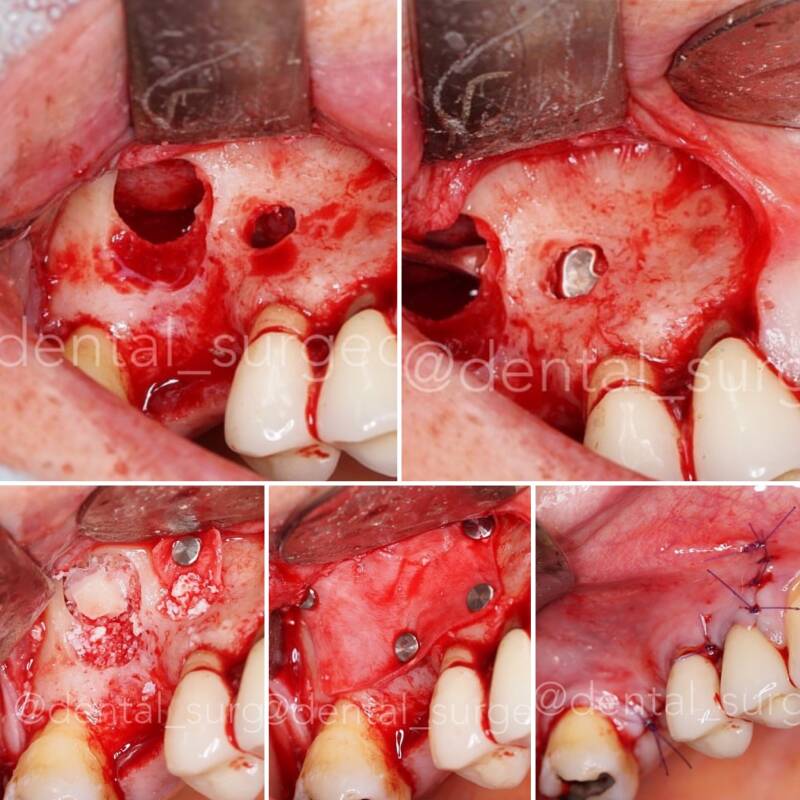

Regeneracion Osea

y

Elevacion de Seno

Regeneracion osea, aumento horizontal y vertical (Khoury, Reabsorbible, no reabsorbible, mallas de titanio... etc)

Elevacion de seno acceso lateral y crestal minimamente invasiva

ACCESO LATERAL

Miles de Elevaciones de Seno siempre con el mismo protocolo de exito.

Todo tipo de situaciones clínicas:

- Diseño de ventana quirúrgica

- Protocolo de elevación de membrana

- Fresado de implante

- Pasos en el relleno

- Cierre y sutura